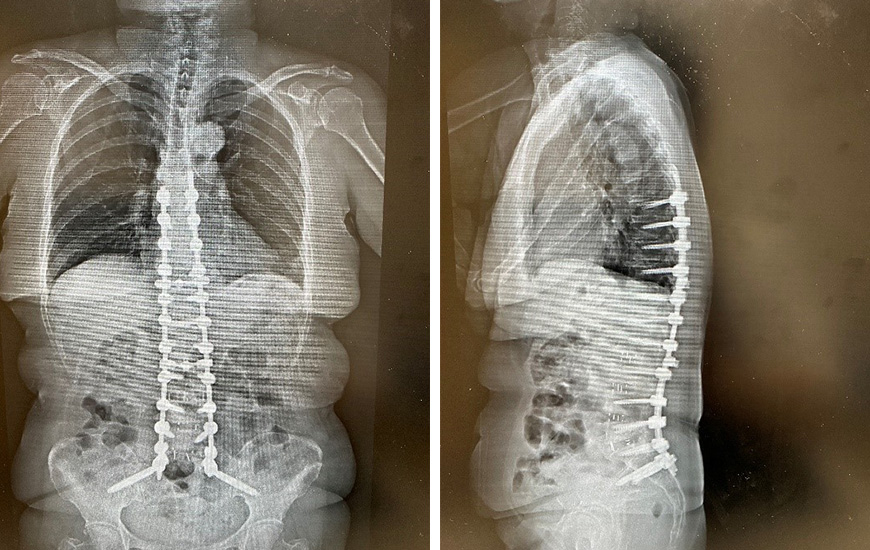

成人脊柱変形に対する治療を行った画像の変化を紹介いたします。

左(手術後正面)写真:背骨に多数のスクリューと椎間板の代わりを入れて背中はまっすぐに戻りました。

左(手術後正面)写真:背骨に多数のスクリューと椎間板の代わりを入れて背中はまっすぐに戻りました。右(手術後側面)写真:背中のくびれ(腰椎前弯)ができて生理的なカーブになっています。

このような手術を行うと、腰の痛みや姿勢の崩れでまっすぐ立っていられなかった患者様が、長時間立てるようになります。